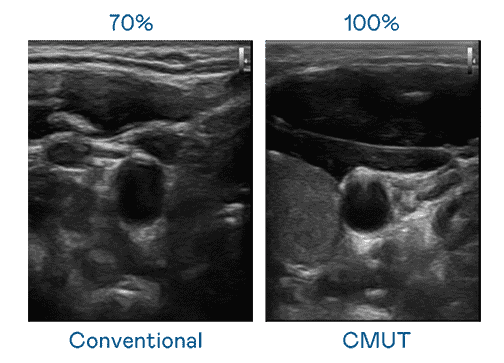

CMUT 技术是一种用电容式微机电元件来产生超音波讯号的技术。。与传统 PZT 压电式技术相比,,,CMUT 频宽增加 30%,,,,更宽频的超音波讯号让影像解析度大幅提升,,,是实现高影像品质医疗超音波扫描、、促进精准医疗发展的关键技术。。。

大频宽带来超清晰影像

超音波影像的解析度高低,,首先取决于探头能发出的讯号频宽。。尊龙集团 CMUT 可提供高清晰的超音波讯号,,,,提供高频宽、、、、高灵敏度、、、、影像纹理细节更高的超音波影像,,协助医护人员缩短影像判读时间及利用精准的医疗影像进行诊断。。。。